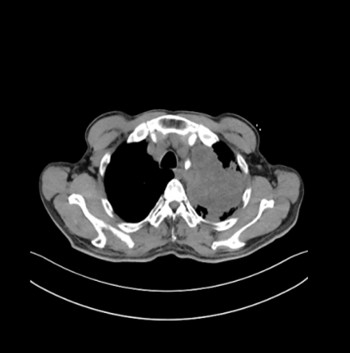

胸部CT示左上肺占位